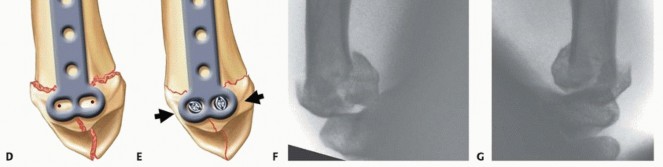

Closed Reduction and Percutaneous Pinning (CRPP)

CRPP is the treatment of choice for classic Bennett fractures where the volar-ulnar fragment is too small to reliably accept a lag screw, yet the joint can be anatomically reduced closed. The reduction maneuver is highly specific, designed to counteract the deforming forces of the APL and Adductor Pollicis. Longitudinal traction is applied to the thumb, followed by palmar abduction and pronation. Direct pressure is then applied to the dorsal-radial aspect of the metacarpal base, effectively pushing the shaft back into the anatomic cradle of the intact volar-ulnar fragment.

Once anatomic reduction is confirmed via multi-planar fluoroscopy, percutaneous fixation is achieved. Typically, two 0.045-inch or 0.062-inch Kirschner wires are utilized. The first wire is driven from the dorsal-radial aspect of the metacarpal shaft directly into the trapezium, effectively neutralizing the proximal pull of the APL. A second wire is often placed transversely from the first metacarpal shaft into the second metacarpal to control rotation and maintain the web space. Pins are cut outside the skin and capped to facilitate easy removal in the clinic.

Image